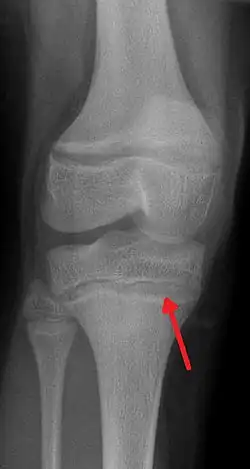

| An X-ray demonstrating the characteristic finding of lead poisoning in humans—dense metaphyseal lines. | |

Exposure to lead can occur through contaminated air, water, dust, food, or consumer products.[2] Lead poisoning poses a significantly increased risk to children and pets as they are far more likely to ingest lead indirectly by chewing on toys or other objects that are coated in lead paint.[2] Additionally, children absorb greater quantities of lead from ingested sources than adults. Exposure at work is a common cause of lead poisoning in adults, with certain occupations at particular risk.[7] Diagnosis is typically by measurement of the blood lead level.[2] The Centers for Disease Control and Prevention (US) has set the upper limit for blood lead for adults at 10 μg/dL (10 μg/100 g) and for children at 3.5 μg/dL;[8] before October 2021 the limit was 5 μg/dL.[9][10] Elevated lead may also be detected by changes in red blood cells or dense lines in the bones of children as seen on X-ray.[4]

Blood lead levels are an indicator mainly of recent or current lead exposure, not of total body burden.[210] Lead in bones can be measured noninvasively by X-ray fluorescence; this may be the best measure of cumulative exposure and total body burden.[40] However, this method is not widely available and is mainly used for research rather than routine diagnosis.[106] Another radiographic sign of elevated lead levels is the presence of radiodense lines called lead lines at the metaphysis in the long bones of growing children, especially around the knees.[211] These lead lines, caused by increased calcification due to disrupted metabolism in the growing bones, become wider as the duration of lead exposure increases.[211] X-rays may also reveal lead-containing foreign materials such as paint chips in the gastrointestinal tract.[29][211]